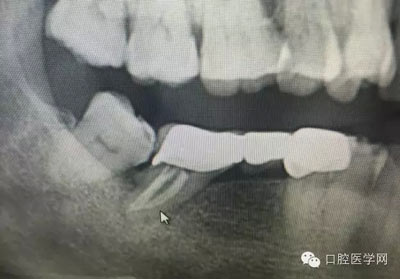

這是一例外院樹脂修復(fù)后十個(gè)月出現(xiàn)牙髓炎癥狀的患者。遇到這樣子的患者大家會(huì)怎么做,證明選擇,還有就是可做可不做治療的如何去平衡。

根管治療,我們在大學(xué)的時(shí)候就學(xué)習(xí)的東西,標(biāo)準(zhǔn)就在那里放著,可是很多時(shí)候我們熟視無睹,放任我們的想象去做。我們多些重視,多些心思,會(huì)好很多,認(rèn)真對待每顆牙齒。